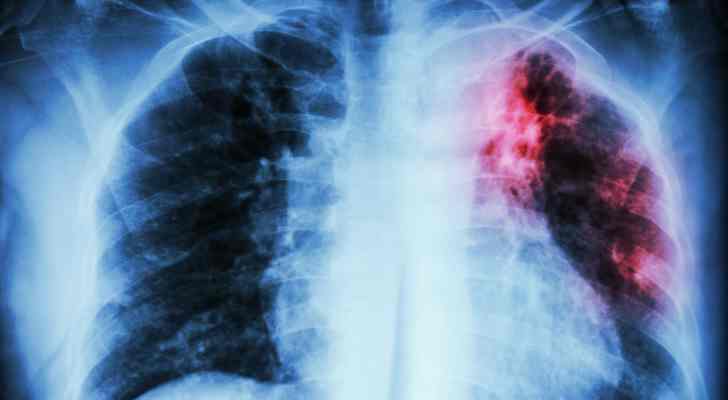

AA type of the disease is a consequence of various chronic infections like tuberculosis. If the person experience rheumatoid arthritis or another inflammatory illness, the chances are also high. It is important to take care of the fundamental problem first.